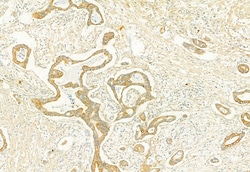

PLCE1 Polyclonal Antibody, Invitrogen™

Antibody detects endogenous levels of total PLCE1.

| Immunocytochemistry, Immunohistochemistry (Paraffin), Western Blot | |

| A synthesized peptide derived from human PLCE1(Accession Q9P212), corresponding to amino acid residues R2267-Q2302. | |